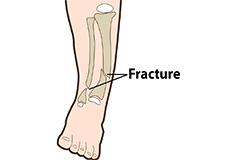

Fractures of the Tibia

The lower leg is made up of two long bones called the tibia and fibula that extend between the knee and ankle. The tibia or shinbone is the larger of the two bones. It bears most of the body’s weight and helps form the ankle joint and knee joint.